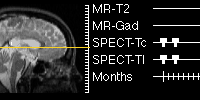

WHOLE BRAIN ATLAS

Well, here we go again into the wacky and wonderful world of the creative scientists. Seems they are forever up to something new and interesting, doesn't it? From the nice folks at Harvard Medical School, here is the Whole Brain Atlas -- everything you ever wanted to know about the human brain... and then some!

In addition to finding lots of good information about the human brain, here you will find great images of real, living brains. Fascinating stuff! You can even look at some MPG movies if your browser is so equipped. And the navigation interface at this Web site really is a work of art -- be sure to look in to this!

Image clips from the Web site Whole Brain Atlas, Harvard Medical School.